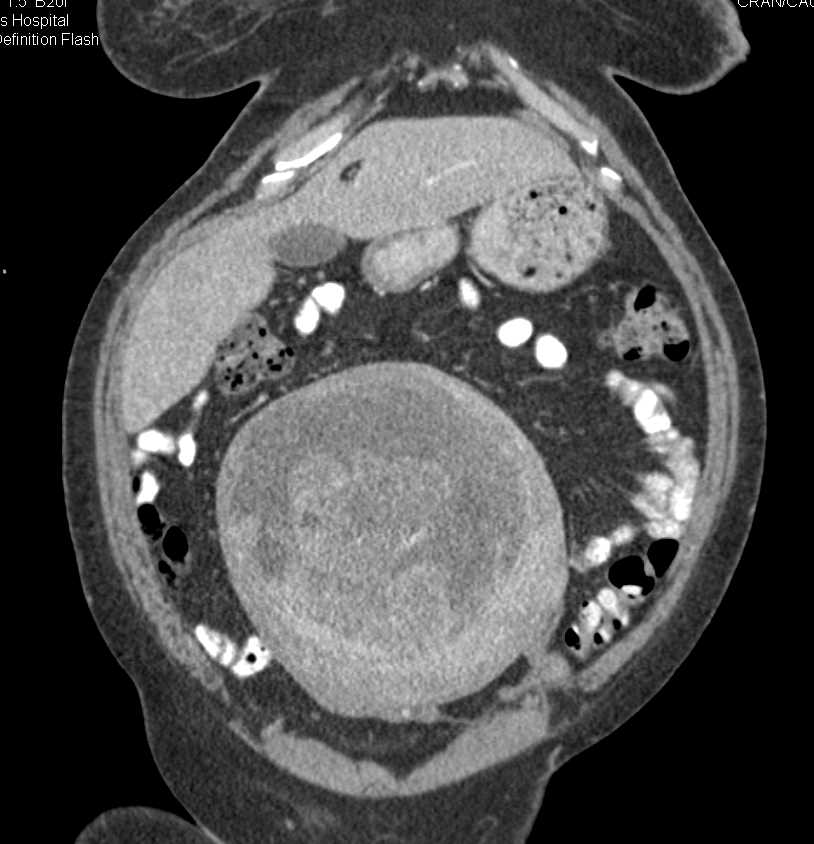

Red degeneration of uterine fibroids in pregnancy Radiology Case

Red degeneration of uterine fibroids in pregnancy Radiology Case from radiopaedia.org

You may experience it as a sharp pain in the abdomen accompanied by. At the lower segment of the uterus, a round heterogeneous structure measuring 11 x 11 x 9 cm with central anechoic material located to the right of the cervix is pushing the cervix. To determine pregnancy outcomes in those previously treated for uterine fibroids, including with uterine artery embolisation and ulipristal acetate. Pain is one of the most reported symptoms of fibroids during the latter part of pregnancy: Pain of carneous degeneration of a uterine. Although red degeneration of a uterine myoma during pregnancy is. Apr 25, 2016 · submucosal fibroids, on the other. Seeing red degeneration in uterine fibroids in pregnancy: Difficulty with bowel movements, or other bowel symptoms.

Those women who are familiar with the symptoms of fibroids will find the symptoms from degeneration are even worse. Before pregnancy degenerating fibroid discharge. At the lower segment of the uterus, a round heterogeneous structure measuring 11 x 11 x 9 cm with central anechoic material located to the right of the cervix is pushing the cervix. Two began to degenerate while i was pregnant last year. Throughout pregnancy, pain is the most common issue caused by fibroids, and may occur in the pelvis, abdomen, lower back, hip, or down the leg. To discuss the mode of delivery in women with a previous myomectomy. Severe cramps, similar to menstrual cramps. For most women studied, fibroids stayed the same size after the second trimester or even shrunk during the third trimester. As the pregnancy progresses, large.